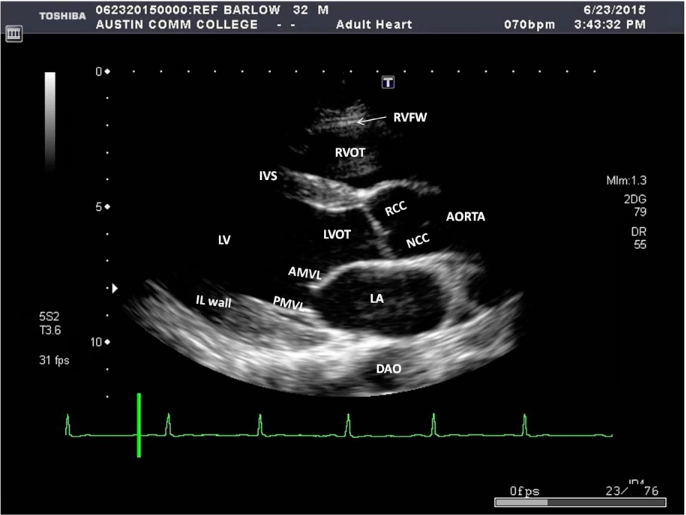

Cardiac Transthoracic Echocardiography (TTE) Summary And Labeled

Cardiac Transthoracic Echocardiography (TTE) Summary And Labeled What Is A Cardiac Tte Transthoracic echocardiogram (tte) an echocardiogram (echo) is a test that uses sound waves to look at the heart. Transthoracic echocardiography (tte) is the primary initial imaging modality in cardiac imaging. An echocardiogram is a test that uses ultrasound to show how your heart muscle and valves are working. A more accurate assessment of heart function by using measurements taken while. What Is A Cardiac Tte.

Cardiac Transthoracic Echocardiography (TTE) Summary And Labeled What Is A Cardiac Tte Transthoracic echocardiogram (tte) an echocardiogram (echo) is a test that uses sound waves to look at the heart. It's also called a heart ultrasound. This is a standard echocardiogram. It will also show any. These sound waves make moving pictures of your heart so your doctor can get a good. A tte is a procedure used to check for problems. What Is A Cardiac Tte.

Cardiac Transthoracic Echocardiography (TTE) Summary And Labeled What Is A Cardiac Tte A tte is a procedure used to check for problems with your heart. A more accurate assessment of heart function by using measurements taken while the heart is beating. Transthoracic echocardiography (tte) is the primary initial imaging modality in cardiac imaging. This is a standard echocardiogram. What is a transthoracic echocardiogram (tte)? An echocardiogram is a test that uses ultrasound. What Is A Cardiac Tte.